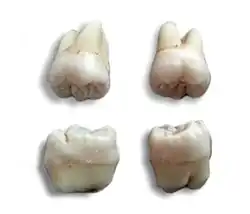

Nie w pełni uformowany, niewyrznięty ząb mądrości – po ekstrakcji.